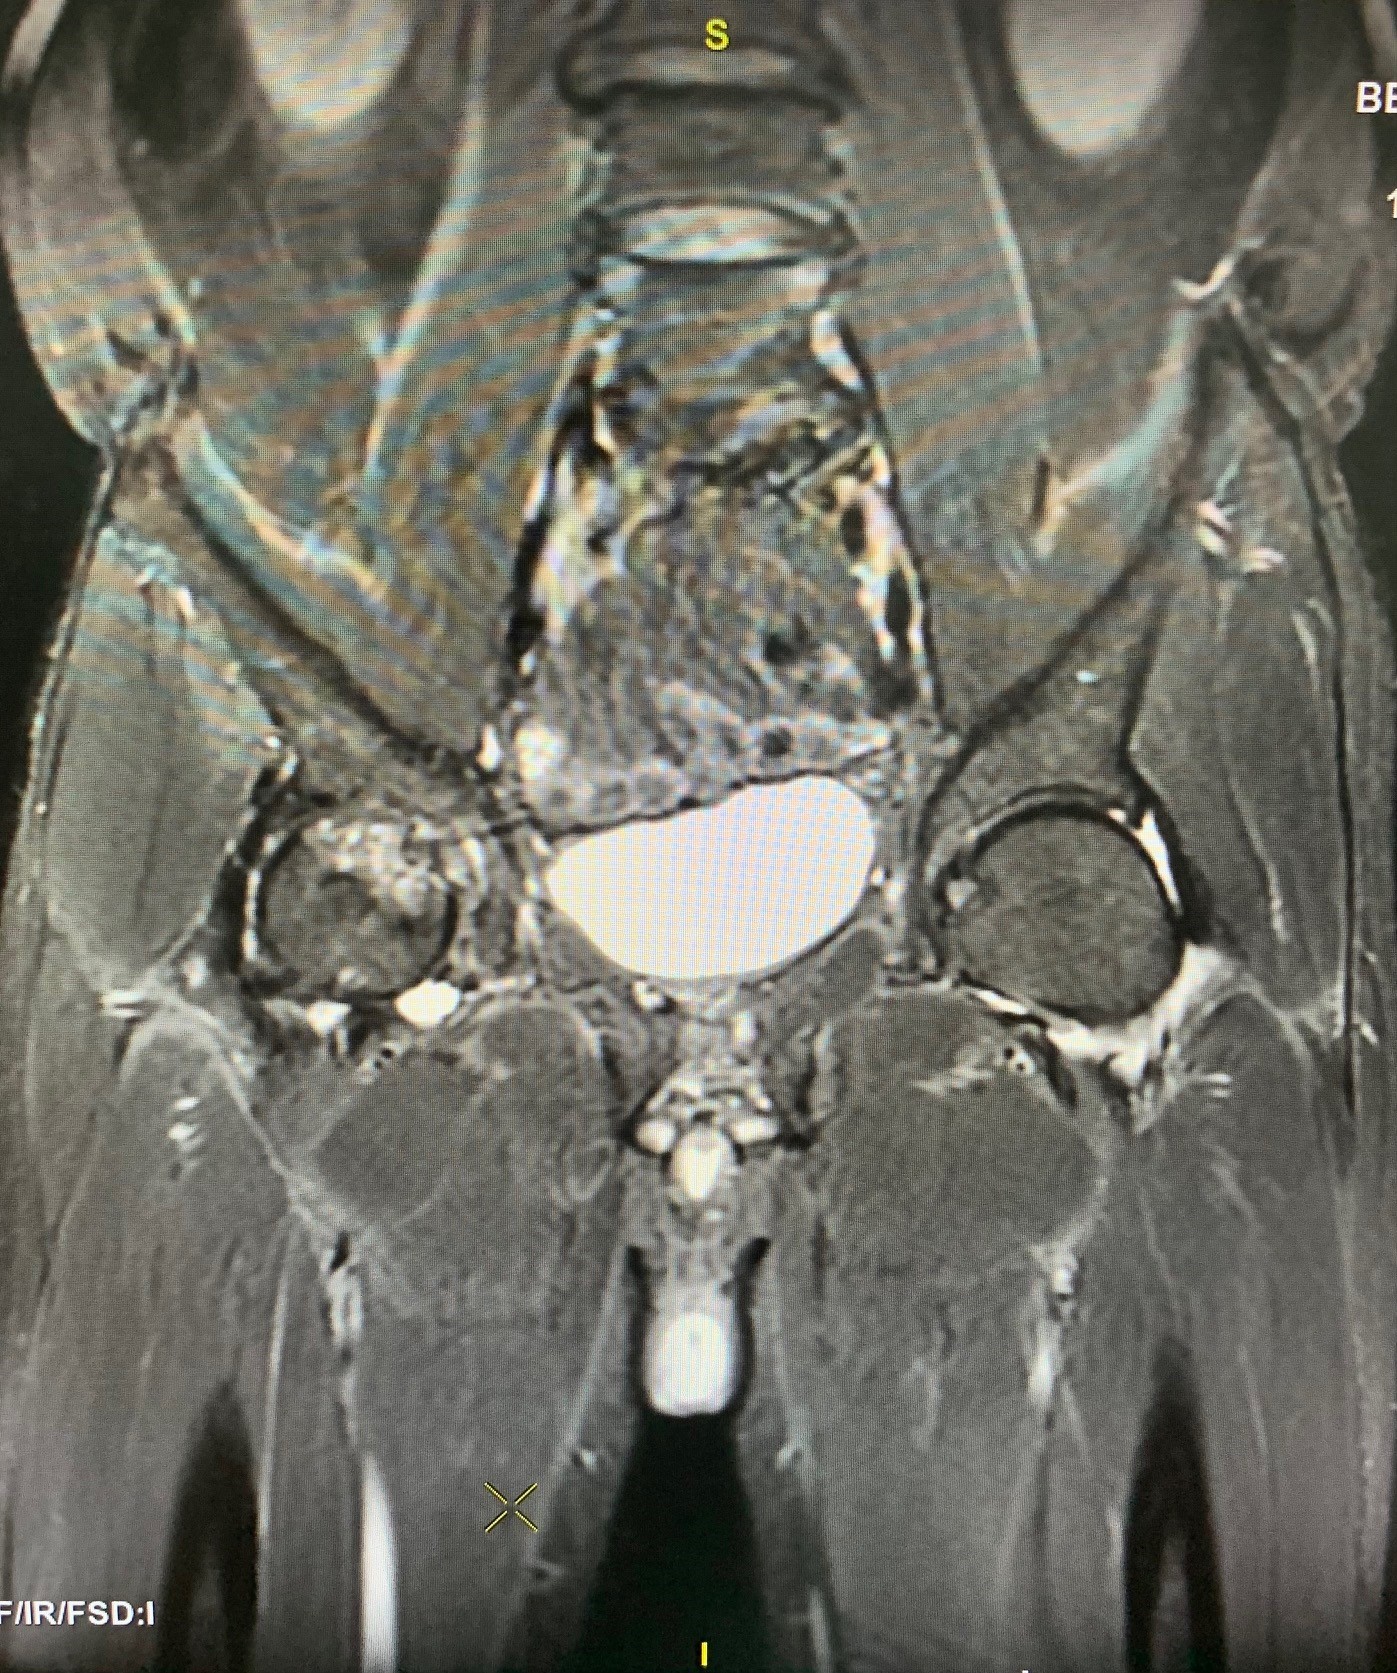

Patient NVT (28 years old, Binh Thuan province) was admitted to the Institute of Orthopedics, Military Hospital 175 with pain in the femur and the inability to walk normally. Through clinical examination, the doctor discovered that the patient had femoral head necrosis on both sides, in a severe stage.

Lieutenant Colonel, Dr. Phan Dinh Mung - Director of the Institute of Orthopedics and Traumatology, Deputy Director of Military Hospital 175 said that recently, the hospital has performed free hip replacements for 50 patients, at a cost The fee was coordinated by a group of doctors from Chicago, USA. Currently, at the Institute of Orthopedics, Military Hospital 175, the rate of young patients with femoral head necrosis is about 12%, a very high rate compared to the world average. Worryingly, the number of young patients with bilateral femoral head necrosis is also increasing.